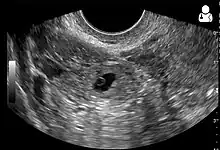

An ultrasound showing a gestational sac with fetal heart in the fallopian tube has a very high specificity of ectopic pregnancy. It involves a long, thin transducer, covered with the conducting gel and a plastic/latex sheath and inserted into the vagina.[33] Transvaginal ultrasonography has a sensitivity of at least 90% for ectopic pregnancy.[5] The diagnostic ultrasonographic finding in ectopic pregnancy is an adnexal mass that moves separately from the ovary. In around 60% of cases, it is an inhomogeneous or a noncystic adnexal mass sometimes known as the "blob sign". It is generally spherical, but a more tubular appearance may be seen in case of hematosalpinx. This sign has been estimated to have a sensitivity of 84% and specificity of 99% in diagnosing ectopic pregnancy.[5] In the study estimating these values, the blob sign had a positive predictive value of 96% and a negative predictive value of 95%.[5] The visualization of an empty extrauterine gestational sac is sometimes known as the "bagel sign", and is present in around 20% of cases.[5] In another 20% of cases, there is visualization of a gestational sac containing a yolk sac or an embryo.[5] Ectopic pregnancies where there is visualization of cardiac activity are sometimes termed "viable ectopic".[5]

Transvaginal ultrasonography of an ectopic pregnancy, showing the field of view in the following image

A "blob sign", which consists of the ectopic pregnancy. The ovary is distinguished from it by having follicles, whereof one is visible in the field. This patient had an intrauterine device (IUD) with progestogen, whose cross-section is visible in the field, leaving an ultrasound shadow distally to it.- Ultrasound image showing an ectopic pregnancy where a gestational sac and fetus has been formed